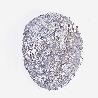

UROTHELIAL CANCER - Protein expressioni

A mouse-over function shows sample information and annotation data. Click on an image to view it in a full screen mode. Samples can be filtered based on level of antibody staining by selecting one or several of the following categories: high, medium, low and not detected. The assay and annotation is described here.

Note that samples used for immunohistochemistry by the Human Protein Atlas do not correspond to samples in the TCGA dataset.

Antibody stainingi

Antibody staining in the annotated cell types in the current human tissue is reported as not detected, low, medium, or high, based on conventional immunohistochemistry profiling in selected tissues. This score is based on the combination of the staining intensity and fraction of stained cells.

Each image is clickable and will lead to virtual microscopy that enables deeper exploration of all samples and also displays staining intensity scores, fraction scores and subcellular localization as well as patient and tissue information for each sample.

Antibody HPA000848

Antibody HPA000868

Antibody CAB025843

Staining

High

Medium

Low

Not detected

Intensity

Strong

Moderate

Weak

Negative

Quantity

>75%

75%-25%

<25%

None

Location

Nuclear

Cytoplasmic/membranous

Cytoplasmic/membranous,nuclear

Urothelial carcinoma, High grade

Urothelial carcinoma, Low grade